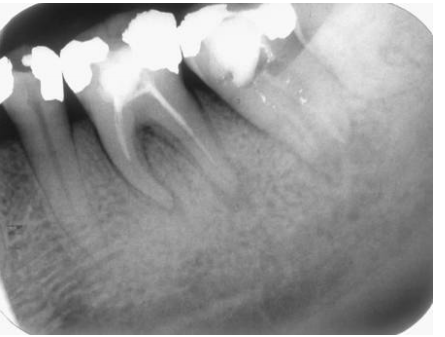

4.23歲男性患者,主訴前牙唇側牙齦在2個星期前長出牙齦膿腫(gum boil),一直沒有消失,該牙 於3年前曾接受過根管治療,並以假牙贋復之。我們以牙膠針偵測(tracing),發現膿腫源自左上 正中門牙(如下圖X光片所示),請問這顆牙齒根尖周圍的診斷為何?

(A)急性根尖牙周炎(acute apical periodontitis) (B)急性根尖膿腫(acute apical abscess) (C)慢性根尖牙周炎(chronic apical periodontitis) (D)慢性根尖膿腫(chronic apical abscess)